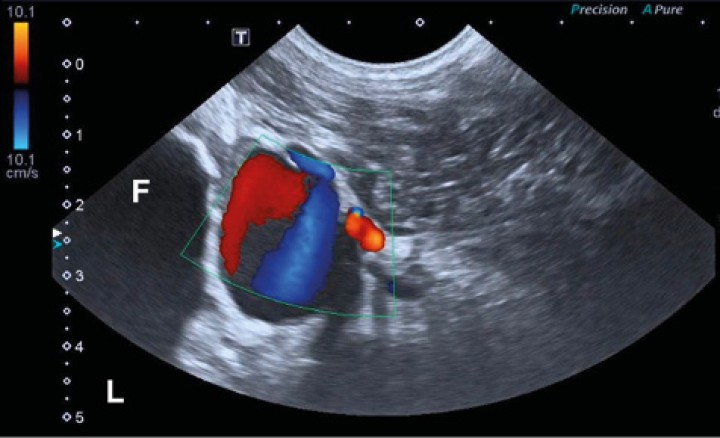

Se exploró ecográficamente la zona diafisaria del fémur derecho (Toshiba Xario 200, Canon Medical, Madrid) utilizando una sonda microconvexa con rango de frecuencias de 6 a 11 MHz. Se visualizó la lesión ósea descrita en otras pruebas. La cortical era irregular y discontinua, con un halo hipoecoico en el tejido blando. Junto a ella se halló una estructura hipoecoica redondeada y de pared fina (Fig. 4, video 1). La señal Doppler color de esta lesión era positiva con apariencia de remolino con color alternante rojo y azul (“signo de ying-yang”) (Fig. 5, video 2).

<p>Imagen ecográfica en plano transversal con empleo de Doppler color en la región caudodistal de la diáfisis del fémur derecho. Se observa una estructura redondeada que produce un efecto de remolino en el Doppler color (signo “ying-yang”). “L”: lateral; “F”: fémur.</p>

Figura 5

Imagen ecográfica en plano transversal con empleo de Doppler color en la región caudodistal de la diáfisis del fémur derecho. Se observa una estructura redondeada que produce un efecto de remolino en el Doppler color (signo “ying-yang”). “L”: lateral; “F”: fémur.